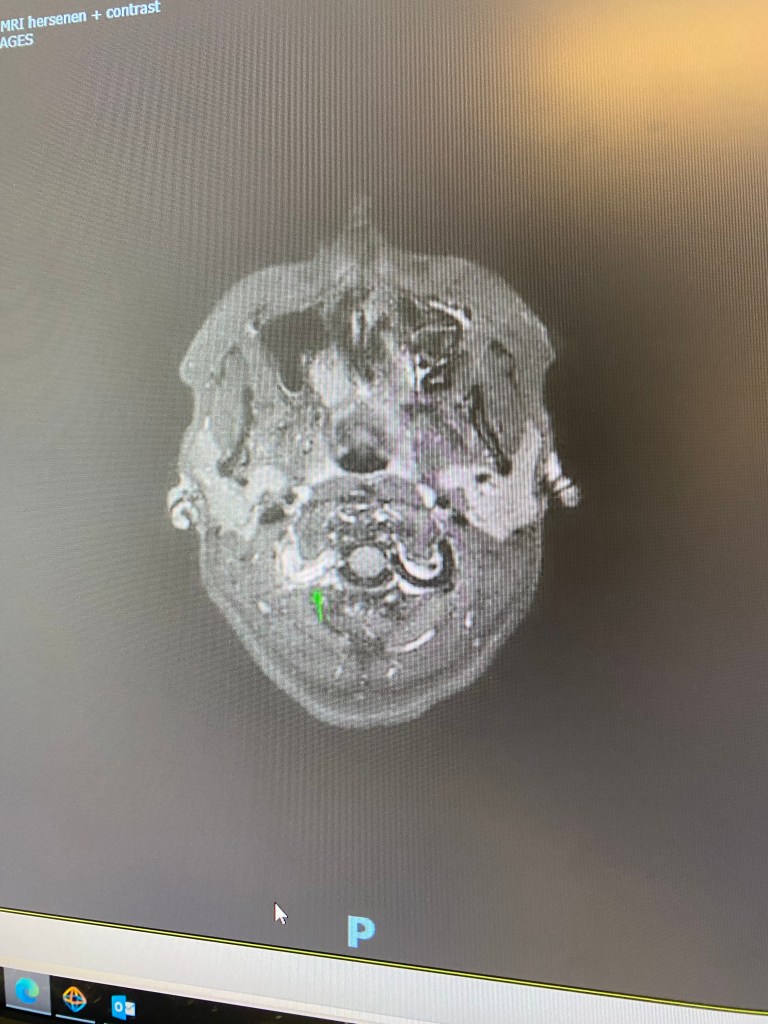

De neuroloog die ik heb gesproken is gespecialiseerd in infarcten bij jongere mensen. Dat was fijn, want ondertussen had ik wel een aantal vragen die beantwoord mochten worden. Ik kreeg de scans te zien van Januari, waarop je goed kon zien waar de beschadigingen zaten. En ik kreeg het verlossende woord over deze aandoening: ik heb géén FMD!